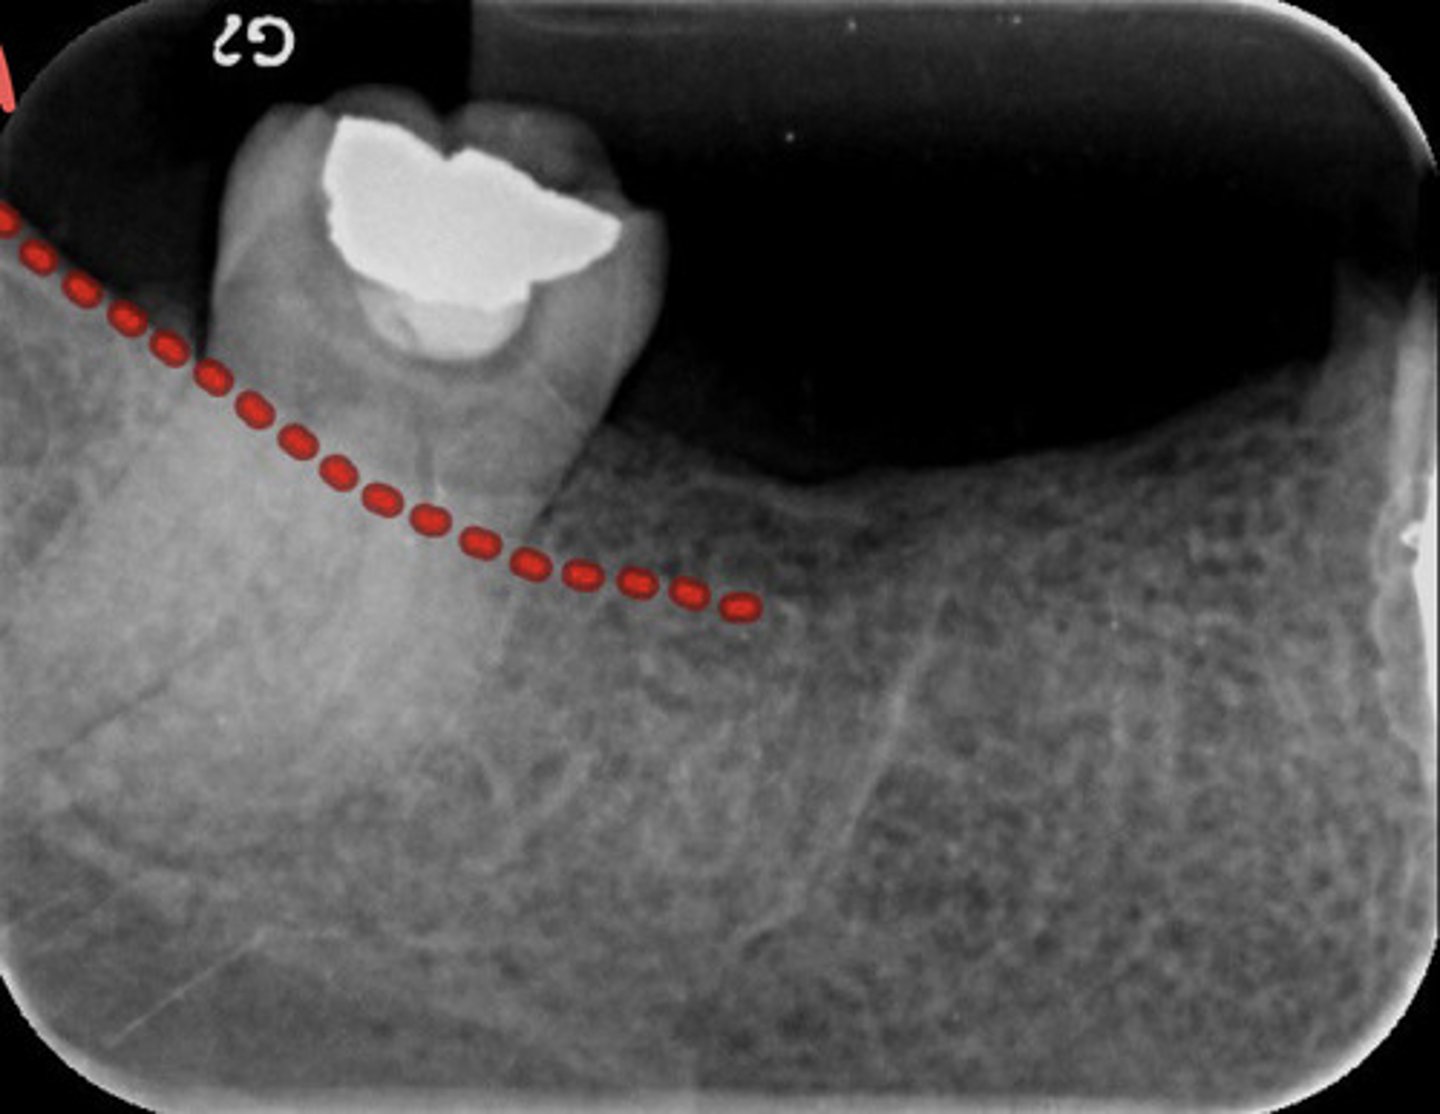

What is the submandibular gland fossa?

information on submandibular gland fossa

radiolucent area in the molar region below the mylohyoid ridge

What does the submandibular gland fossa look like radiographically?

What does the inferior border of the mandible look like radiographically?

information on inferior border of the mandible

radiopaque band of bone

-only see if there is a lot of angulation